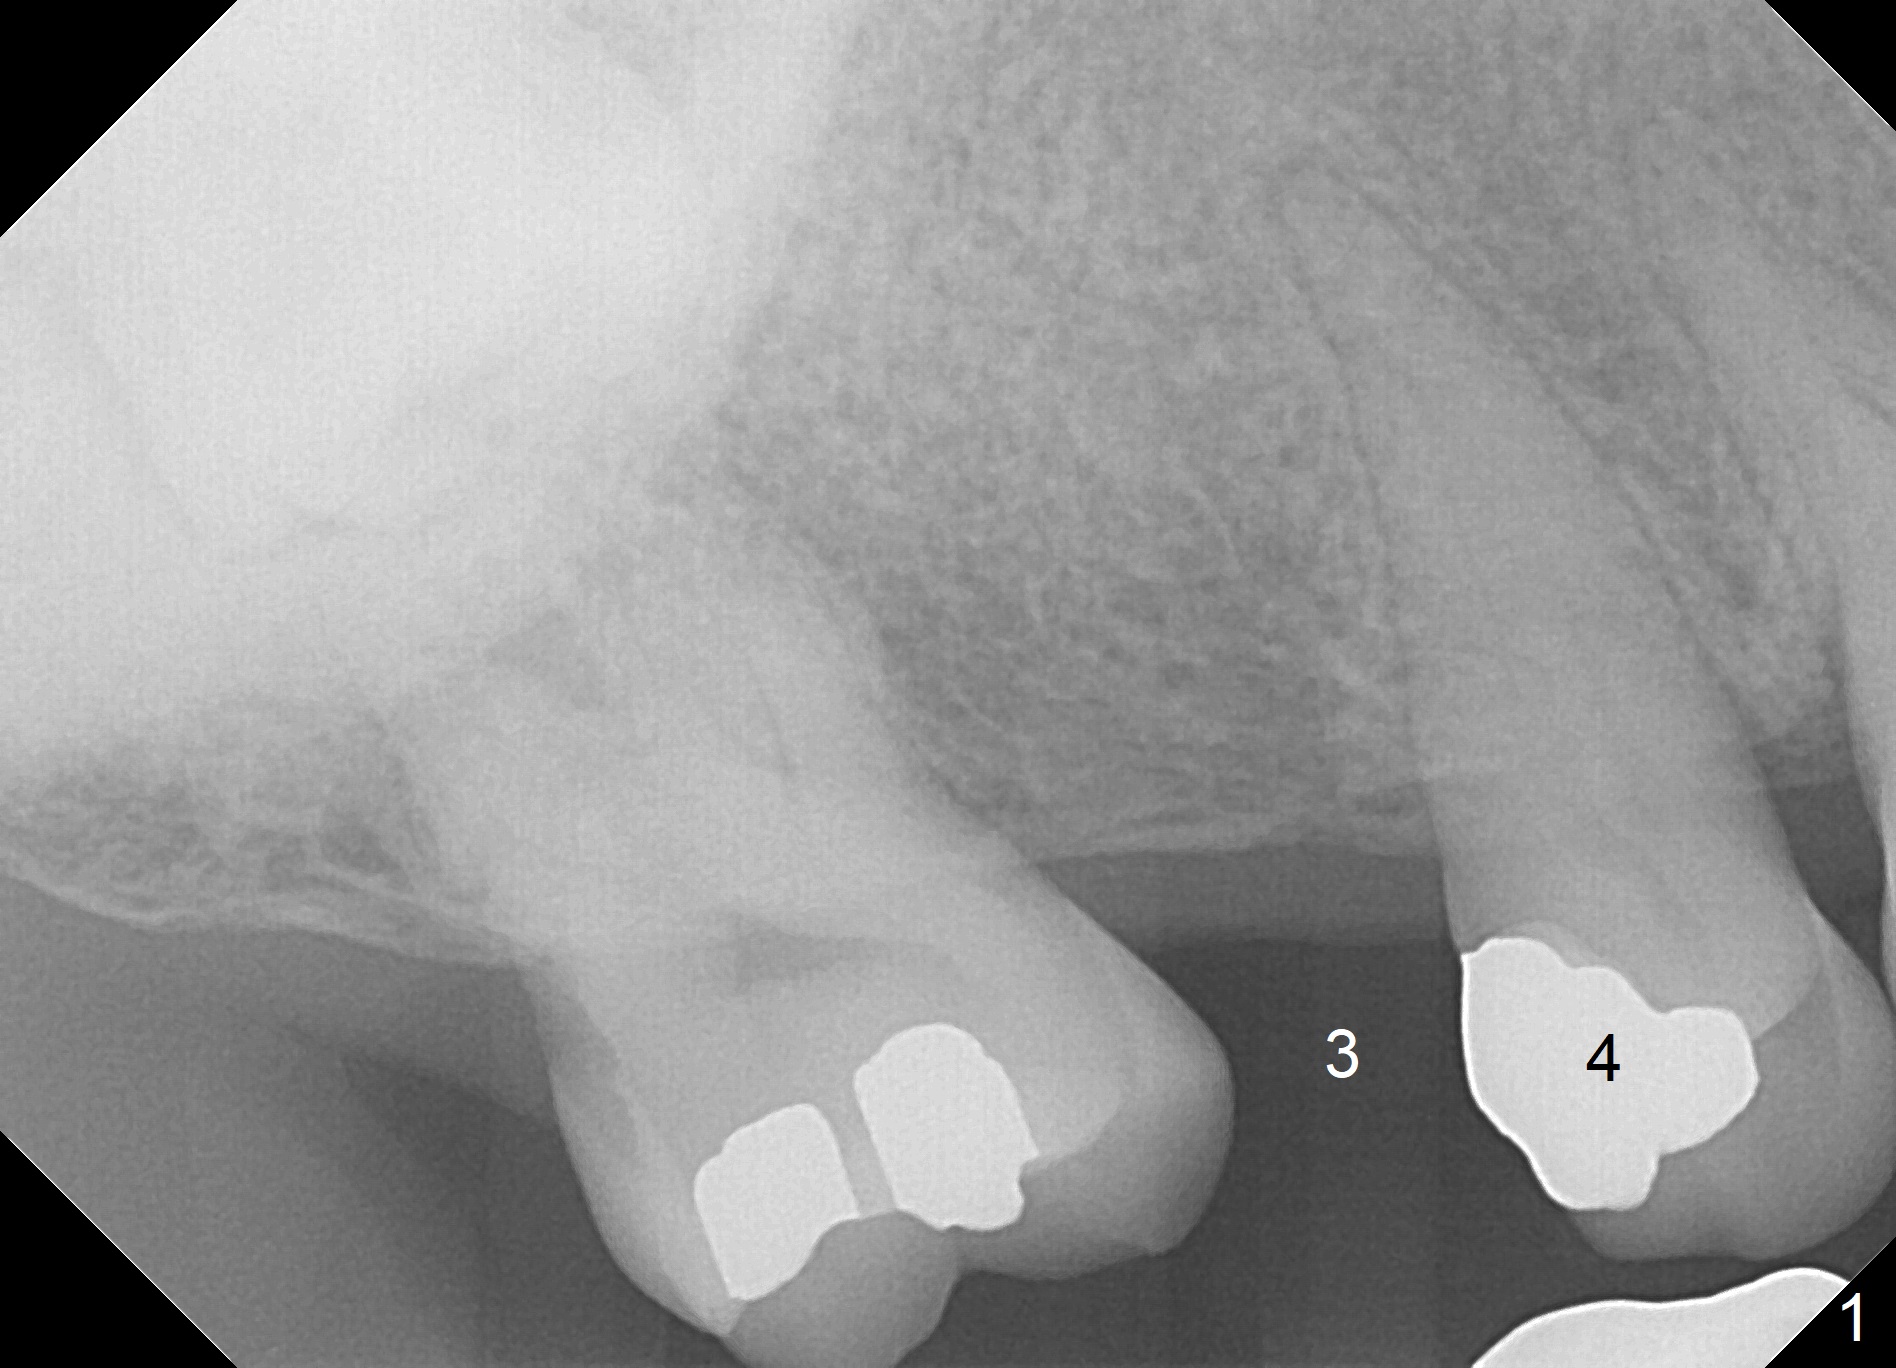

A 62-year-old man has sudden severe pain associated with the tooth #4. Since the edentulous space at #3 is narrow (Fig.1,3), an implant is placed distal to the site of #4 (after extraction) as a molar (Fig.2-4). Use Lindamann bur to remove the bone in the distal wall of the socket prior to osteotomy (Fig.2 red dashed area).